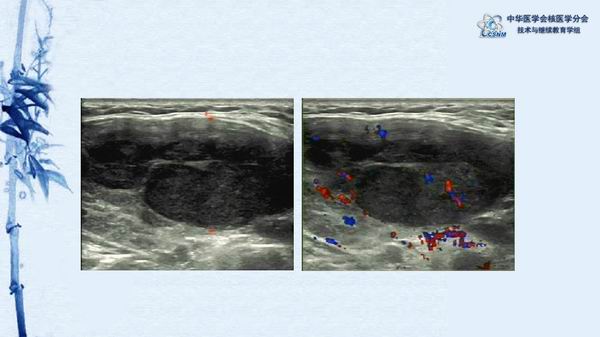

病例80:甲状腺淋巴瘤18F-FDG PETCT显像一例-【CSNM继教学组】余飞 同济大学附属第十人民医院